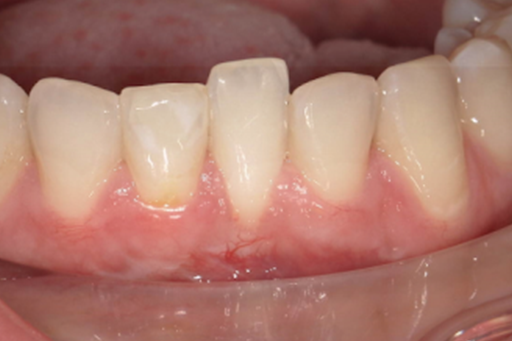

Gingival recession

Gum Disease Treatment